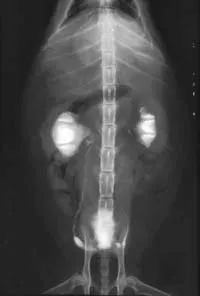

Abdominal radiographs will show only an enlarged kidney or kidneys (Figure 2A), but excretory urography will show renal pelvis dilatation (Figure 2B). Ultrasonography will also show hydronephrosis, renal parenchymal disarray, and necrotic debris in the renal collecting system (Figure 3).

Abdominal radiographs of a cat with bilateral pyonephrosis; a cystotomy performed 6 months previously had caused bilateral ureteral obstruction at the urethral junction (A and B). Pyelography was done by pyelocentesis, and bilateral hydronephrosis is shown.